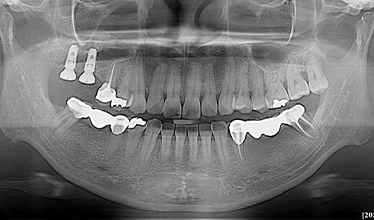

CASE 01

-

임플란트 식립 전 -

임플란트 식립 후 -

임플란트 보철 후